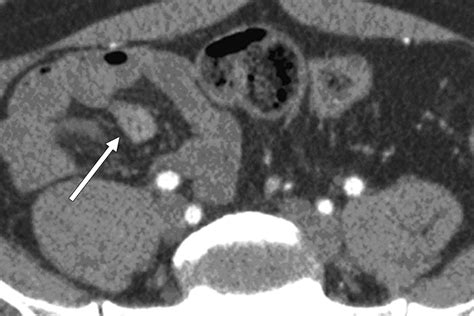

CT Scan Structural imaging of the abdomen Moderate (good for complications like obstruction)

The interpretation of a Meckel’s Diverticulum Scan requires expertise in nuclear medicine. A positive result is indicated by a “hot spot”—an area of increased radioactivity that appears in the lower abdomen during the imaging sequence. This “hot spot” corresponds to the area where the technetium-99m has accumulated in the gastric mucosa.

It is worth noting that a negative scan does not absolutely rule out the presence of a Meckel’s diverticulum. If the diverticulum lacks gastric mucosa or if the blood supply is compromised, the tracer may not accumulate sufficiently to be detected. In such instances, clinicians may consider repeat testing or moving toward surgical options if clinical symptoms are severe and persistent.